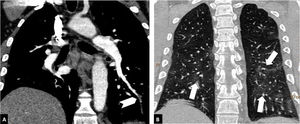

Depending on the location of the most proximal filling defect, thromboembolic involvement was classified as: a) proximal, if the most proximal thrombus was located in the trunk of the pulmonary artery or in the main pulmonary arteries (Fig. 1); b) medial, if the material was located in the proximal lobar or segmental arteries (Fig. 2); or c) distal, if the involvement was distal segmental or subsegmental (Fig. 3).17

Distal pulmonary thromboembolism in a patient with mild parenchymal involvement by COVID-19. Chest CT angiography. A) Filling defect in a basal distal segmental artery of the left lower lobe (white arrow head). B) Ground-glass parenchymal involvement in both lower lobes (arrows), affecting less than 30% of the lung parenchyma.

Severity of involvement was classified according to extent of lesions in the lung parenchyma as: a) normal: no involvement; b) mild: <30% involvement of the lung parenchyma (Fig. 3); c) moderate: 30–60% involvement (Fig. 2); or d) severe: >60% involvement of the lung parenchyma (Fig. 1).20–24